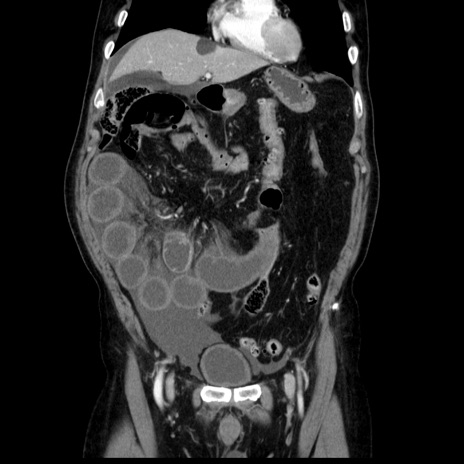

症例30(冠状断像)

【症例】80歳代男性

【主訴】臍周囲痛

【現病歴】約6時間前から臍下部痛が出現。次第に腹部膨隆・背部痛も生じてきたため来院。背部痛の場所は変化しない。

【既往歴】腎盂腎炎

【身体所見】意識清明、BT 36.3℃、BP  131/87mmHg、P 87bpm、SpO2 100%(RA)、臍周囲自発痛・圧痛あり、反跳痛なし、自発痛部位に一致して板状硬あり、腹部膨隆、腸雑音減弱、CVA tenderness両側陰性。

【データ】WBC 19600、CRP 0.33